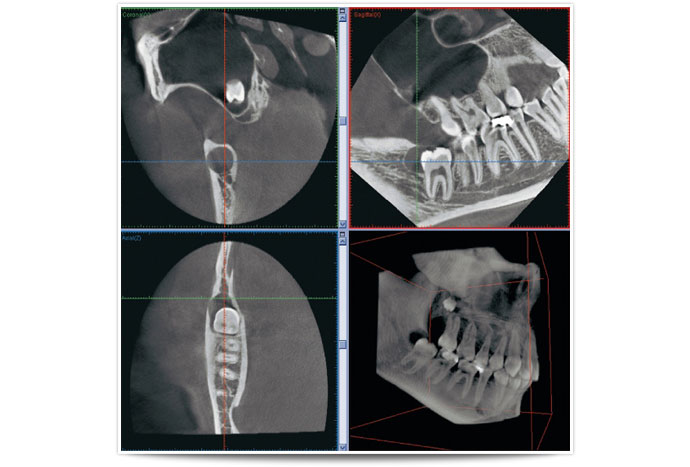

CTとは、立体的(三次元)に骨の状態や神経の位置を把握できる特殊な撮影装置です。

二次元のレントゲン(歯科医院にある通常のレントゲン)では見えなかった事、分からなかった事が、歯科用CTなら正確な診査と診断ができ、安全性と治療のクオリティーを高めることが可能となります。

2次元レントゲンとCT装置との「見え方」の比較をお伝えします。

左の画像が2次元レントゲンで、右の画像がCT画像です。どれも同一の患者様の画像です。

根尖病巣という歯の根の病気を診断するために2つの装置で撮影を行いました。

マークがついている部分が根尖病巣部分です。

二次元レントゲンではうっすらとしか映っておらず判断に迷う部分ですが、CTでははっきりと映し出されています。

医療において「見える」「見えない」は治療クオリティーに大きな差が出ます。ましてや外科手術を伴うインプラントにおいてはなおさらです。これまでのインプラント事故は、歯科医師の未熟が大きな原因を占めますが、CT撮影を行わず、あいまいな状態で(二次元レントゲンのみの診断)オペを遂行したことにより生じてしまった事故もあります。

インプラント手術においてCT撮影は必須です。CT撮影を行うか否かも医院を選ぶうえでの判断材料にしていただければと思います。